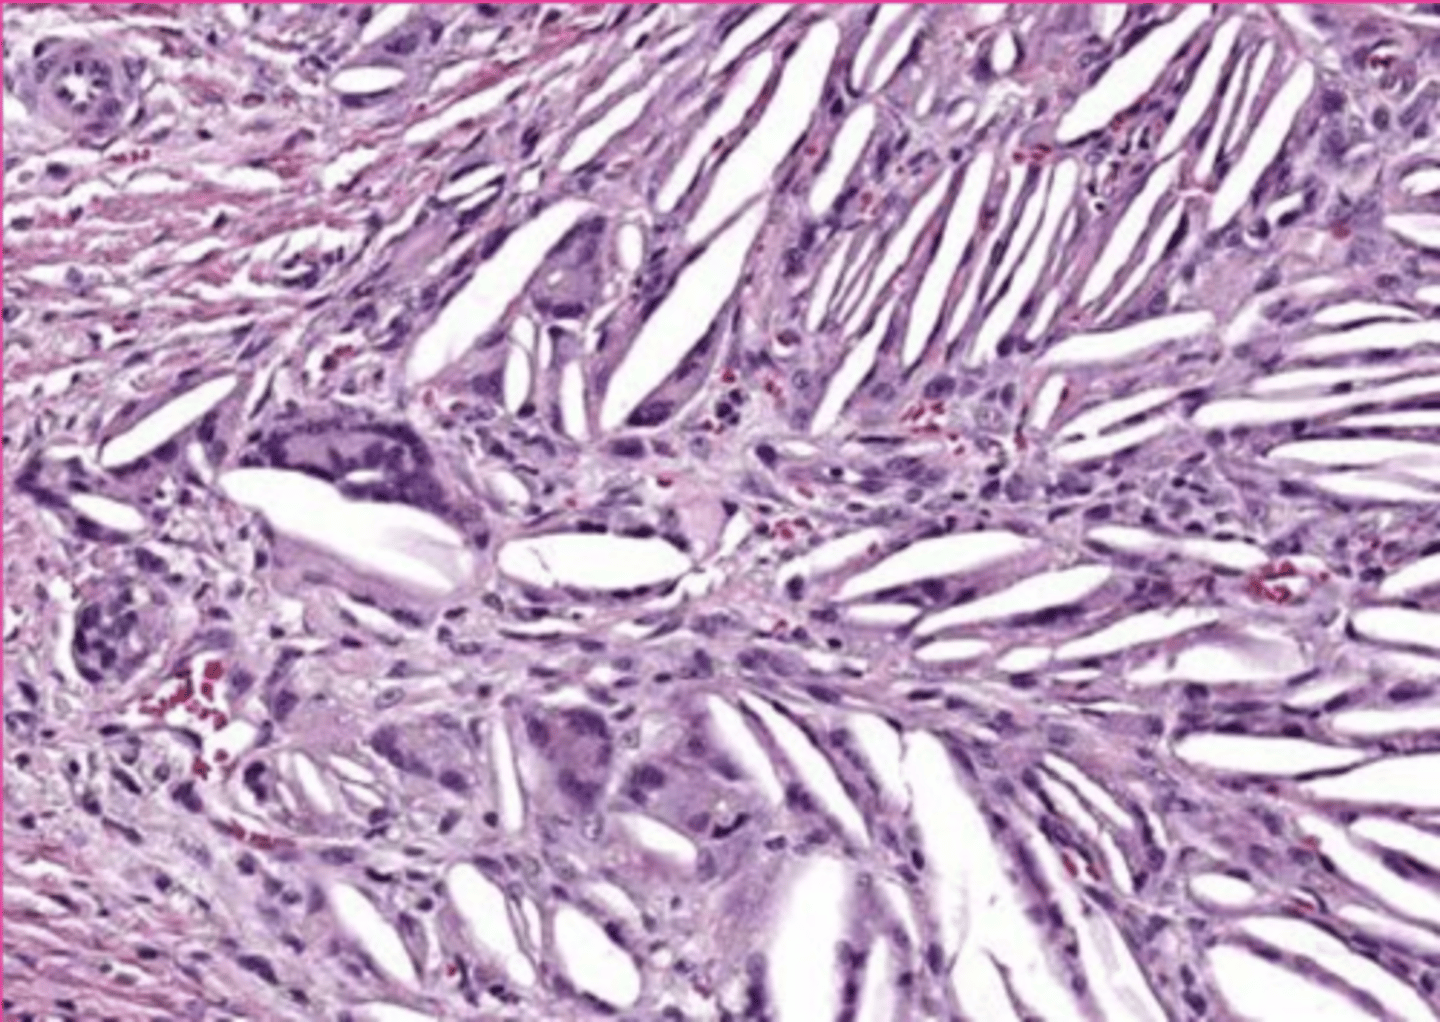

hyaline casts

What extracellular inclusion?

<p>What extracellular inclusion?</p>

8